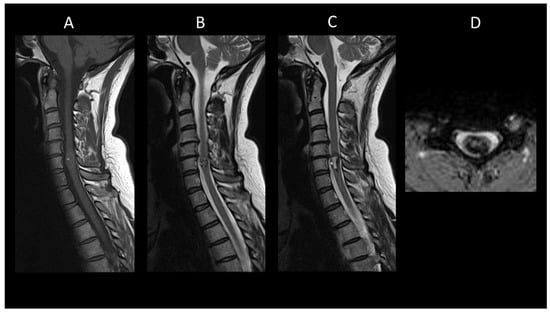

Neuromyelitis Optica Spectrum Disorders Positive for Aquaporin-4 IgG

Myelin-Oligodendrocyte Glycoprotein Antibody Associated Disease

Neurosarcoidosis